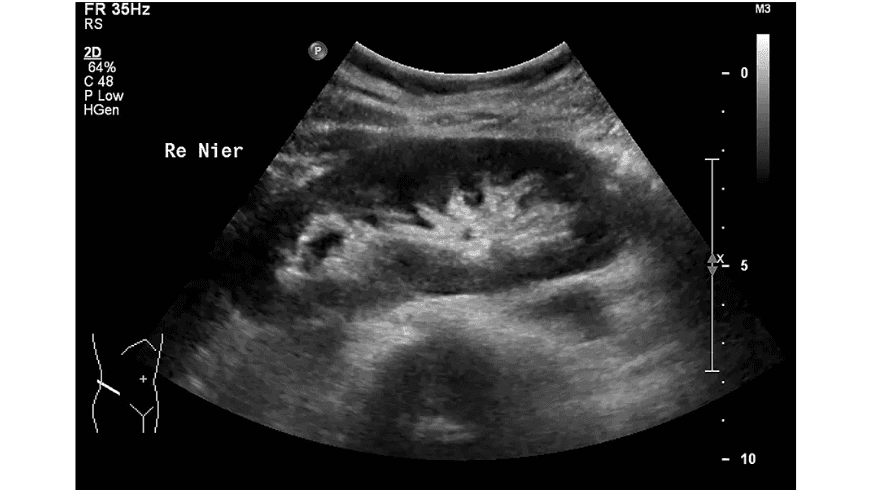

Bloedonderzoek bij nierschade